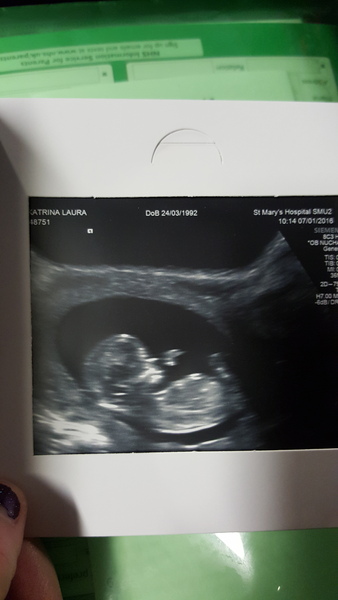

Fab scan pic gx thanks for sharing :)

Lovely scan photo.

Gx91, congrats on scan, lovely pic! And Julfin, glad yours went well too. You must feel so relieved to have had that conversation with your new boss.

Morning everyone. Love your scan pic Gx I have my scan tomorrow, can't wait.

Gx lovely clear scan photo.

Hey everyone haven't had time to catch up so will have a read through later scan went well they've moved me forward a couple of days so due date is now 17th of July baby was so active bouncing around everywhere I'm really excited now xx

Awh, lovely pic, wanting!

Lovely scan wanting congrats.